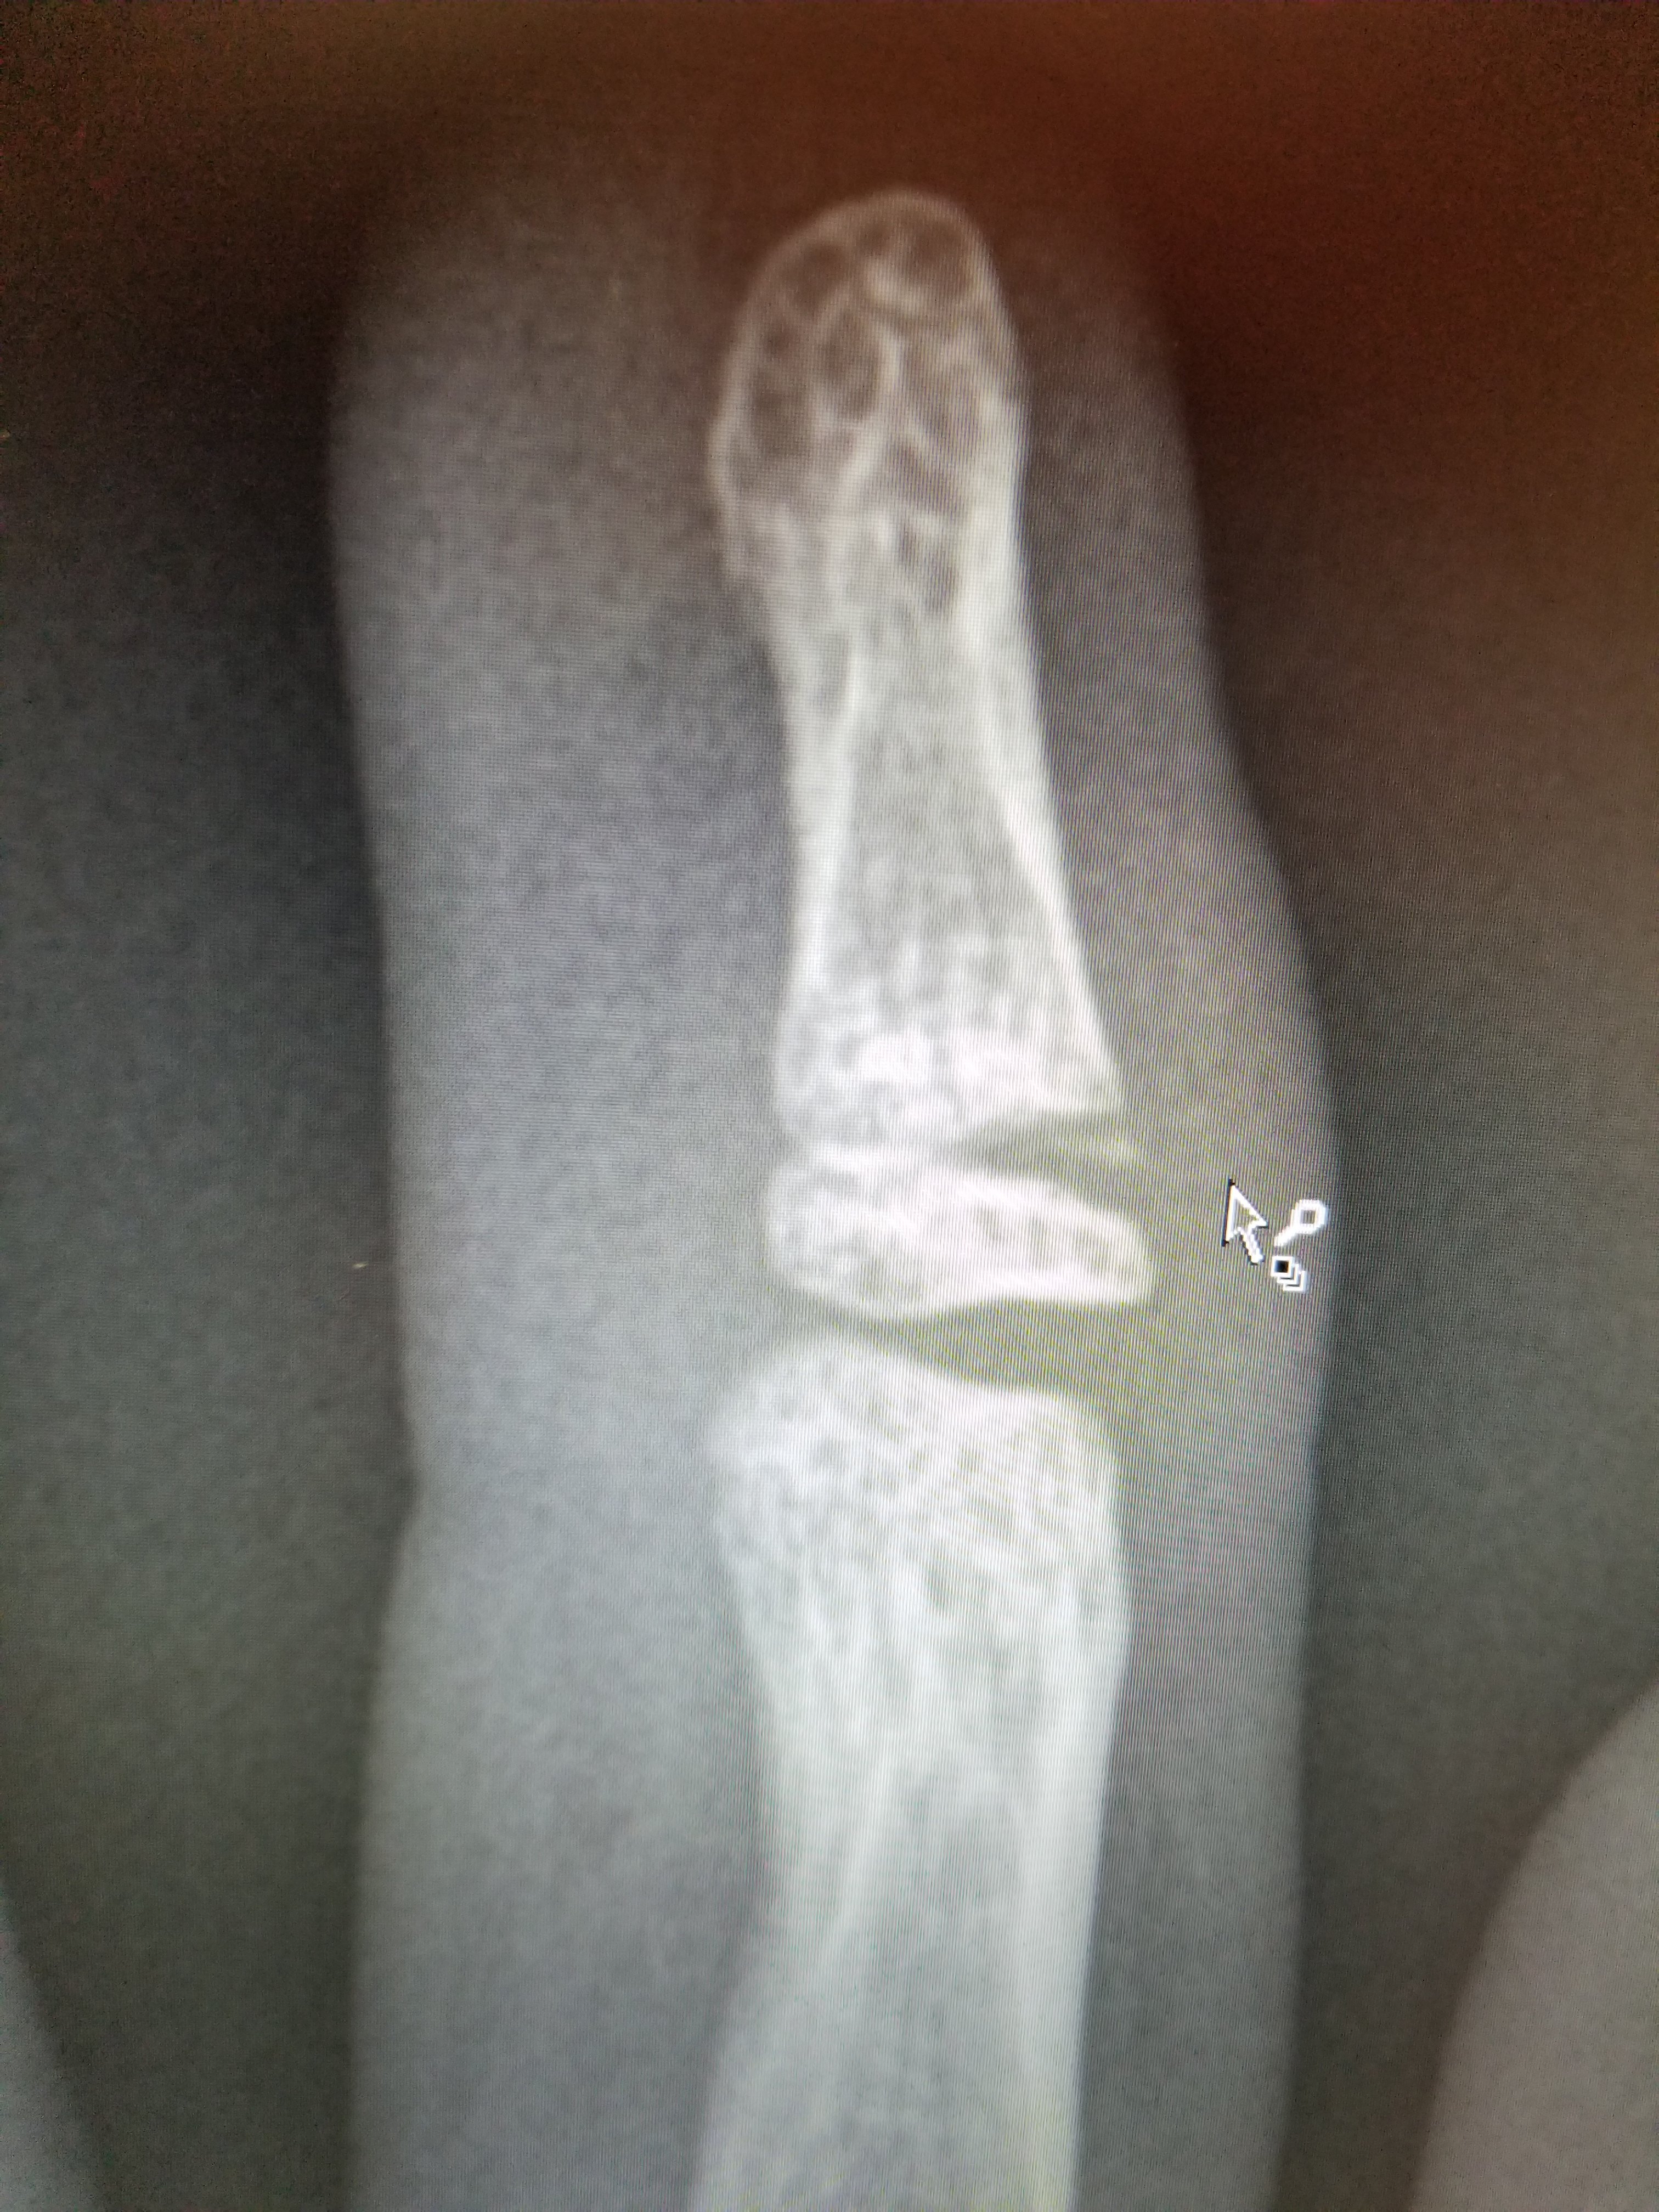

We made great use of the visit by getting him to pull up the PET/CT images so we could check them out. Since we wouldn’t receive the radiologist’s report until Wednesday afternoon, Eli decided to write his own report. Who needs a medical degree for that anyway?

Eli’s report is transcribed below, with the corresponding images (Cancer cells “light up” on the images, but so do some normal things, like the heart, bladder, and brain. They look for asymmetries and things lighting up where they shouldn’t).